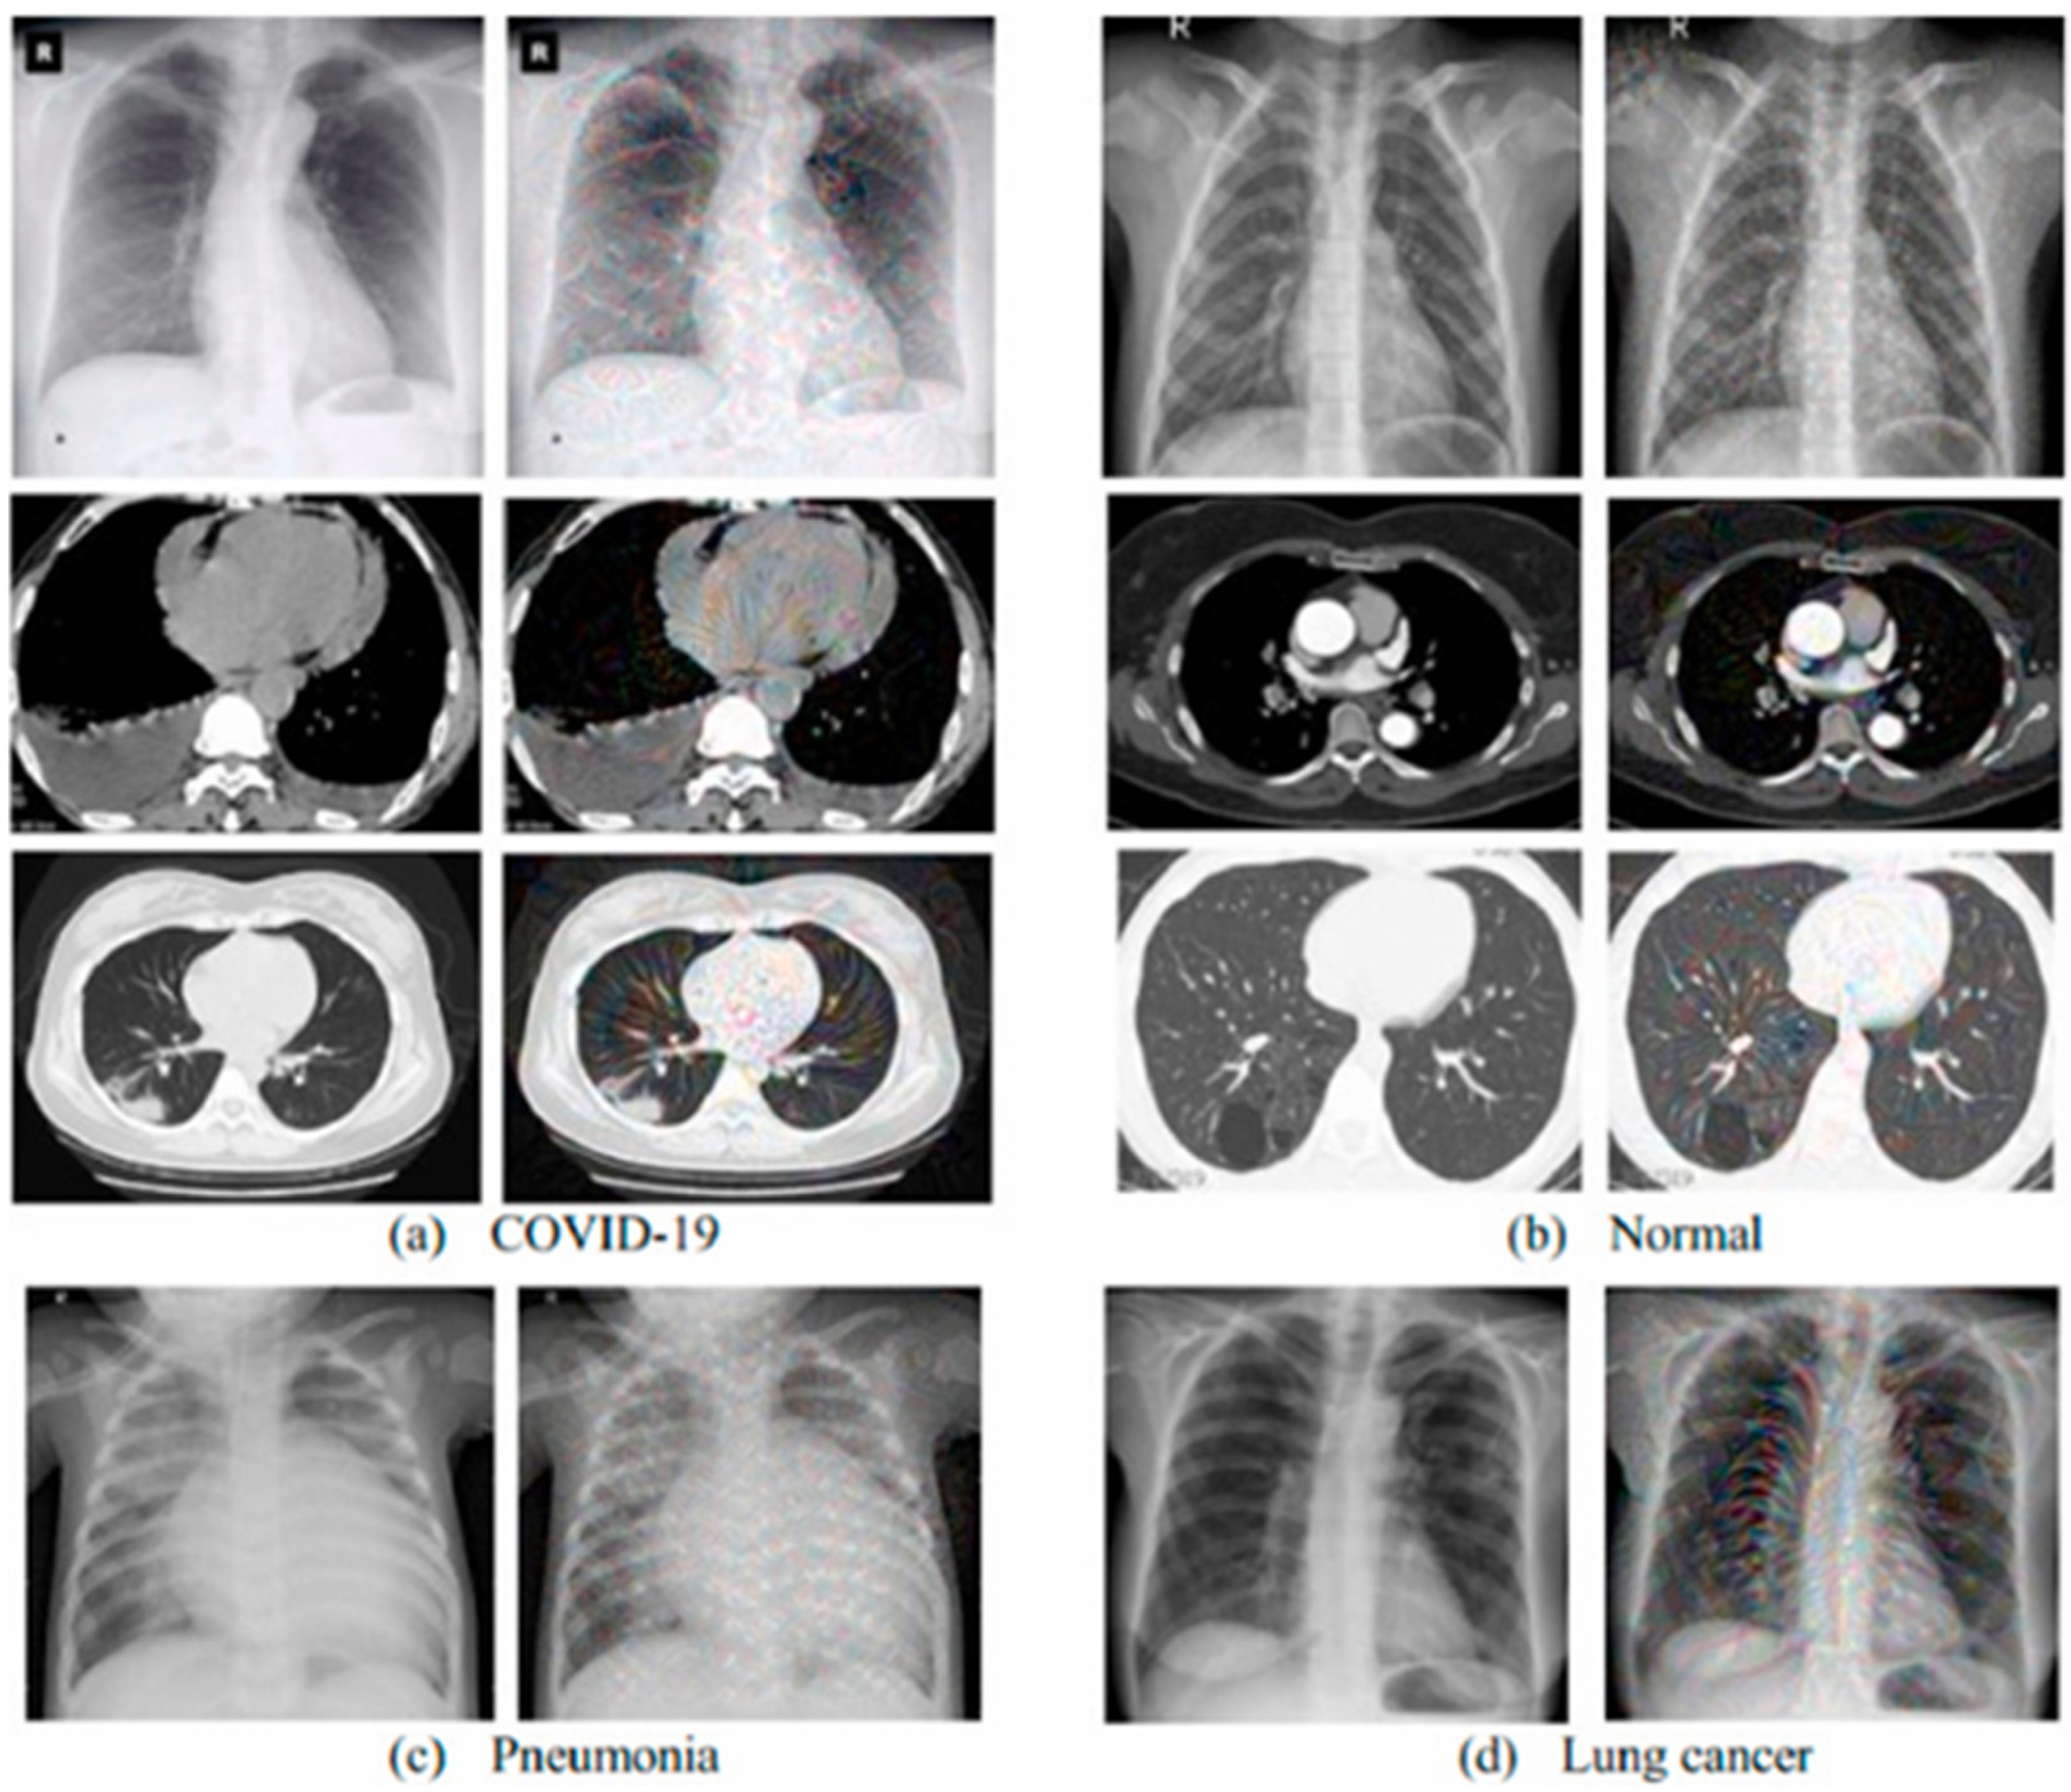

Medical Images for AI COVID-19 Diagnosis

CT and X-ray Medical Images for COVID-19 Diagnosis

Machine Learning (ML) and Deep Learning (DL) for COVID-19 Diagnosis